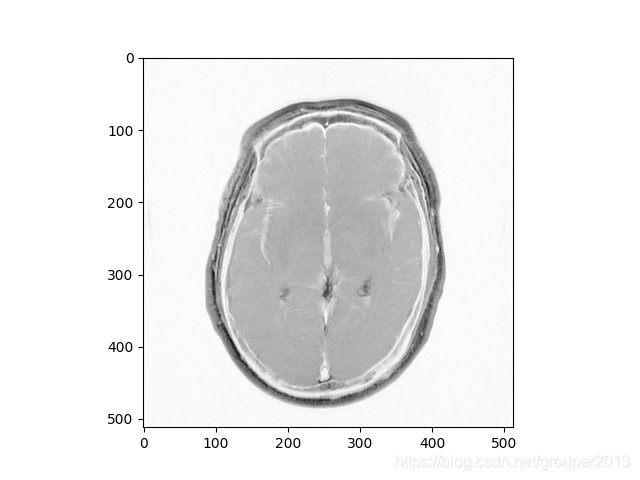

#plt.imshow(pix,'gray_r') #反转灰白图像

结果显示: